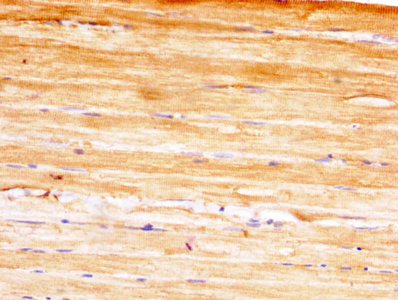

IHC image of CSB-PA02174A0Rb diluted at 1:400 and staining in paraffin-embedded human skeletal muscle tissue performed on a Leica BondTM system. After dewaxing and hydration, antigen retrieval was mediated by high pressure in a citrate buffer (pH 6.0). Section was blocked with 10% normal goat serum 30min at RT. Then primary antibody (1% BSA) was incubated at 4°C overnight. The primary is detected by a biotinylated secondary antibody and visualized using an HRP conjugated SP system.